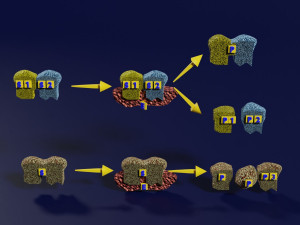

A blend model of brain along with its covering layers (meninges), skull bone and scalp labelled in detail and anatomically precise. The parts depicted are white, gray, pia, arachnoid, dura, bone, skin, fat, aponeurosis, periosteum, falx cerebri and more.